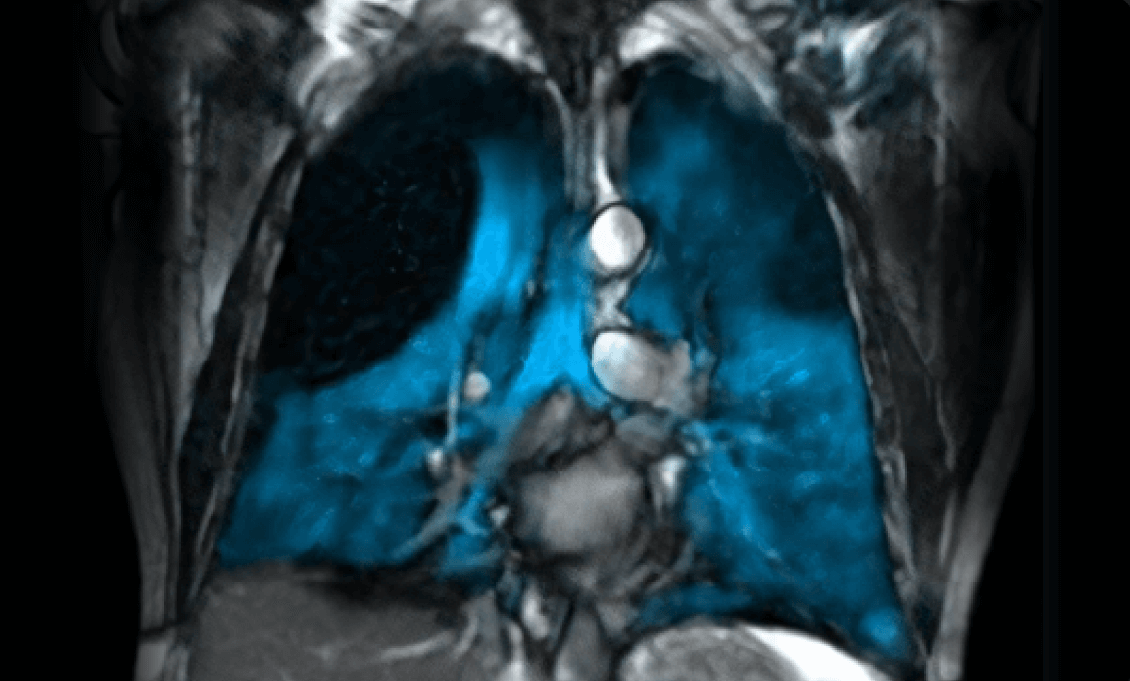

Xenon MRI uses hyperpolarized xenon gas to create detailed functional images of lung ventilation without ionizing radiation, making it safe for both adults and children. The technology, implemented using state-of-the-art hyperpolarizer system, enables visualization of ventilation defects and gas exchange abnormalities invisible to conventional imaging. This opens unprecedented opportunities for early disease detection, treatment monitoring, and research into conditions including COPD, asthma, cystic fibrosis, and post-COVID lung complications.